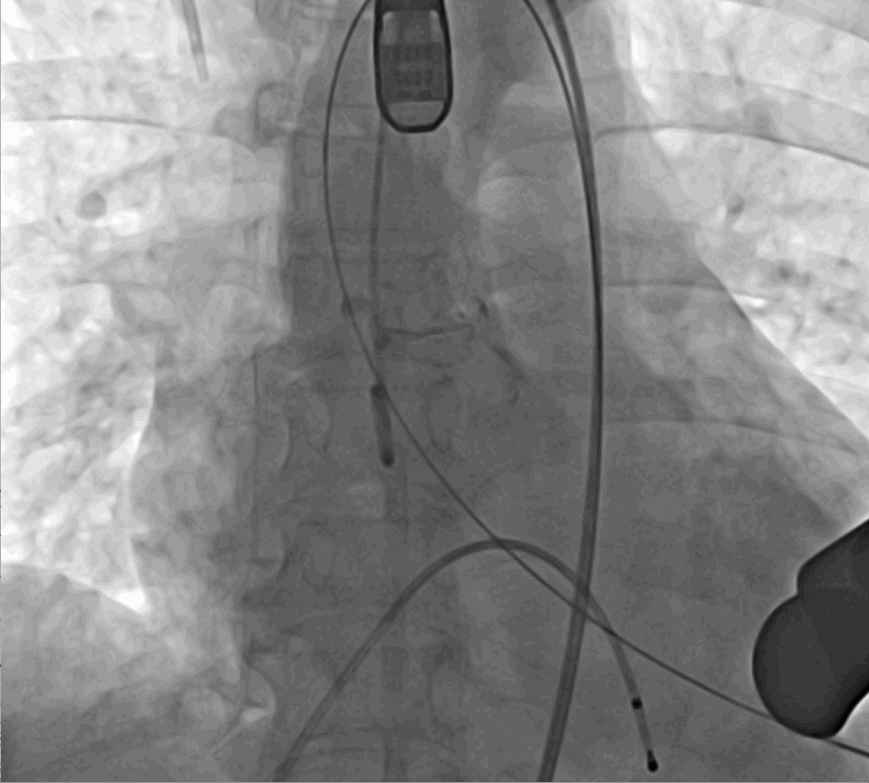

術(shù)中釋放定位鍵后DSA影像圖

手術(shù)采用經(jīng)心尖入路,對患者進行全麻后,在左側(cè)心尖處做3-4cm微創(chuàng)手術(shù)切口,在DSA及超聲引導(dǎo)下手術(shù)順利完成。從導(dǎo)入器械到完成瓣膜置入,僅耗時約10分鐘。術(shù)后即刻主動脈瓣返流程度由術(shù)前大量返流轉(zhuǎn)為消失,患者于導(dǎo)管室拔除氣管插管,次日由ICU轉(zhuǎn)入普通病房。